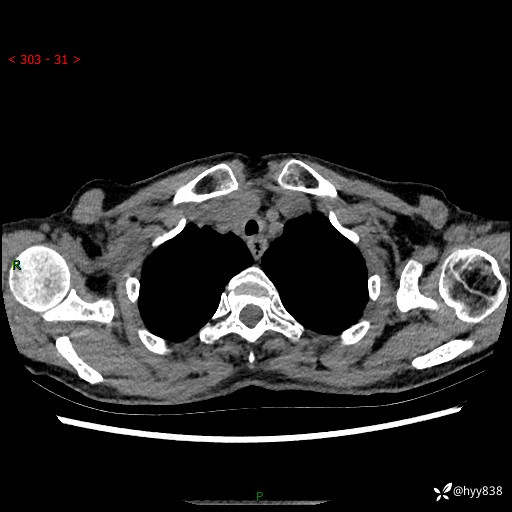

胸部CT平扫+增强